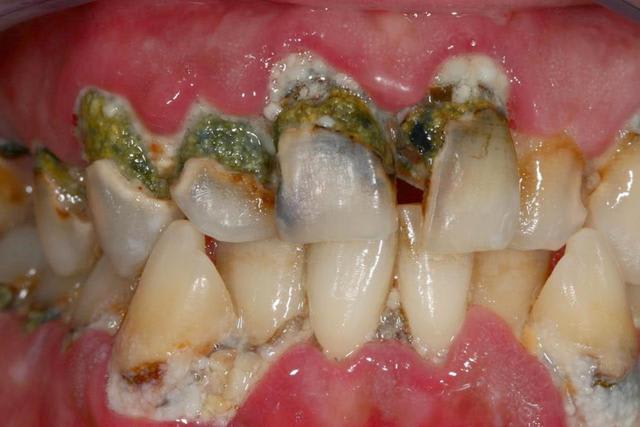

histoire de mettre un peu de couleurs dans ce post monotone...

un peu de vert :) c'est rare ....

Cas classique d'allergie à la brosse à dents.

Je parie...pas de douleur ?

Un cas pour Borst ?